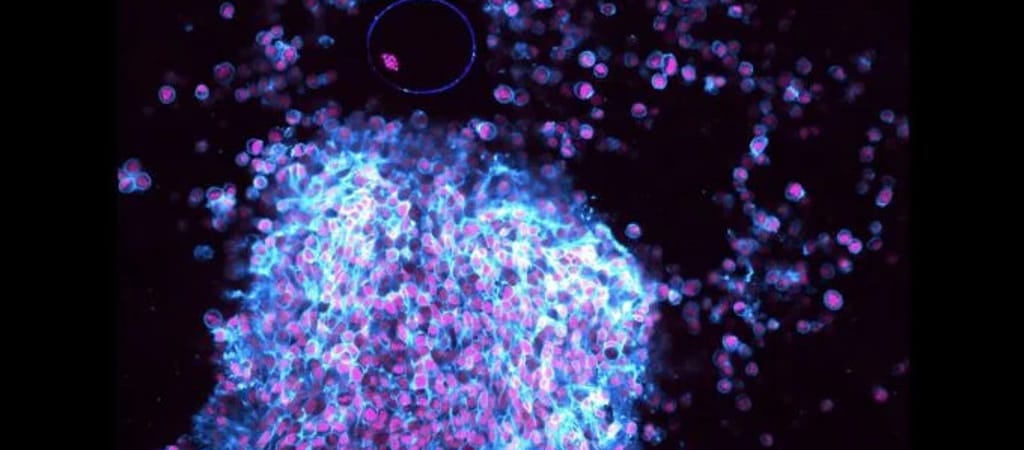

Az intézet szakemberei ugyanakkor ki tudtak dolgozni egy olyan módszert, amivel megfigyelhetővé vált ez a fontos pillanat – és ez több egy érdekes felvételnél, mivel egyszer új termékenységi kezeléseket dolgozhatnak ki a segítésével. De először is, a szóban forgó felvétel:

A Gizmodo kifejti: a petesejtek valamennyi emlősben egy folyadékkal teli üregben, a tüszőben vannak. Egy ciklus során több mint 30 petesejt érik, de csak a legérettebb tud kilökni egyet. Mint a megállapításaikat a Nature Cell Biology tudományos folyóiratban publikáló szakemberek kifejtik: ugyan a múltban a genetikai vizsgálatok, boncolások és a tenyésztett minták segítségével bepillantást nyerhettek a folyamatba, de egyik sem összemérhető egy valódi videófelvétellel.

Hogy egy ilyet elkészíthessenek, a kutatók petefészek-szövetet vettek egerektől, melyeket genetikailag úgy módosítottak, hogy a kamerán is könnyen látható petesejteket termeljenek. A szóban forgó szöveteket egy kameralencsére helyezték, majd megindították az ovulációt két hormon segítségével.

A fentiek segítségével egy olyan, több többlépcsős folyamatot figyelhettek meg, amiben izomösszehúzódások mellett „nagyon specifikus” kémiai anyagok felszabadulása is végbement – végül egy petesejtet eredményezve.

„Három fázist különböztethetünk meg” – magyarázza Melina Schuh, a Max Planck Institute igazgatója, aki maga is részt vett a tanulmány elkészítésében. „A tüsző kitágul, összehúzódik, majd kilöki a petesejtet” – fejti ki.